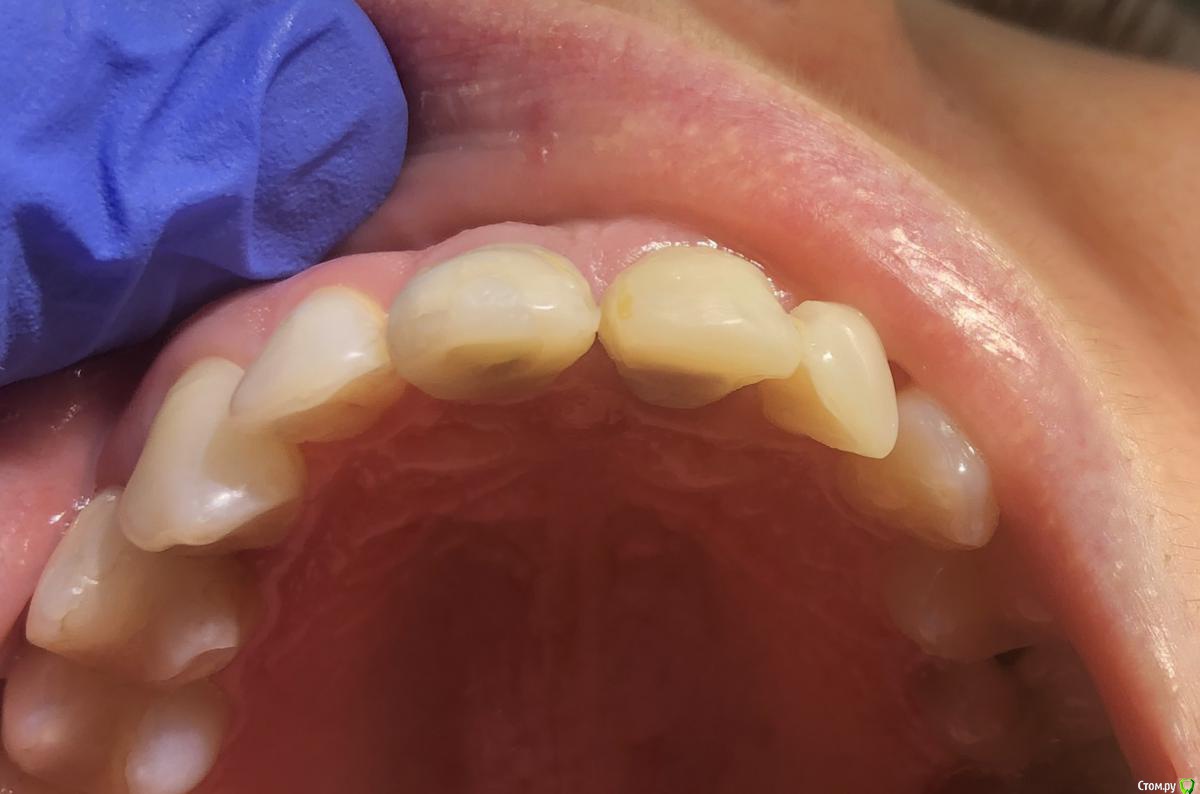

Irouil Опубликовано 2 мая, 2020 Поделиться Опубликовано 2 мая, 2020 Я тоже не вижу, что тут еще давить. У коронки плохой контур в пришеечной части, но ближе к платформе винта коронка должна быть тоньше с таким рентгеном, значит там поддержка тканей еще уменьшится. Судя по оклюзионному снимку в оро-вестибулярном направлении коронке не хватает объёма, зенит тоже апикальнее необходимого. Надо разобраться с соседней 1-кой, если замена там коронки - вариант, то можно рассмотреть апикализацию зенита на зубе на 1 мм в итоге. Но, имхо, без хирургии тут не выйдет ничего Ссылка на комментарий

Александр07 Опубликовано 2 мая, 2020 Автор Поделиться Опубликовано 2 мая, 2020 Я тоже не вижу, что тут еще давить. У коронки плохой контур в пришеечной части, но ближе к платформе винта коронка должна быть тоньше с таким рентгеном, значит там поддержка тканей еще уменьшится.Судя по оклюзионному снимку в оро-вестибулярном направлении коронке не хватает объёма, зенит тоже апикальнее необходимого. Надо разобраться с соседней 1-кой, если замена там коронки - вариант, то можно рассмотреть апикализацию зенита на зубе на 1 мм в итоге.Но, имхо, без хирургии тут не выйдет ничего[/quote Да, коронку будут менять на 2.1, и Зенит думаю на 2.1 тоже сместят, правда на 1.1 если сделать выпуклей профиль как полагается скорее всего там ещё зенит выше уйдёт Тогда если с хирургией работать советуете сразу сделать профиль как полагается на 1.1 , сместить Зенит на 2.1, контакт протяженней между 1.1-2.1, и ждать результата , правильно понял ? Ссылка на комментарий

Irouil Опубликовано 2 мая, 2020 Поделиться Опубликовано 2 мая, 2020 (изменено) Я тоже не вижу, что тут еще давить. У коронки плохой контур в пришеечной части, но ближе к платформе винта коронка должна быть тоньше с таким рентгеном, значит там поддержка тканей еще уменьшится.Судя по оклюзионному снимку в оро-вестибулярном направлении коронке не хватает объёма, зенит тоже апикальнее необходимого. Надо разобраться с соседней 1-кой, если замена там коронки - вариант, то можно рассмотреть апикализацию зенита на зубе на 1 мм в итоге.Но, имхо, без хирургии тут не выйдет ничегоДа, коронку будут менять на 2.1, и Зенит думаю на 2.1 тоже сместят, правда на 1.1 если сделать выпуклей профиль как полагается скорее всего там ещё зенит выше уйдёт Тогда если с хирургией работать советуете сразу сделать профиль как полагается на 1.1 , сместить Зенит на 2.1, контакт протяженней между 1.1-2.1, и ждать результата , правильно понял ?На мой взгляд, надо начать со снятия коронок, изготовления временной на 2.1, модификации временной на имплантате в сторону истончения поддесневой части, потом хирургия с аугментацией в области 1.1, времяхи на место. 3 месяца на подрасти и подсозреть. Дальше меняем контуры времяхи на винте на правильные (повторение контура зуба до зенита и на 1-1.5 мм апикальнее, далее резкое сужение к тибейсу), ждем еще пару недель. На оставшуюся разницу планируем редукционную хирургию на 2.1 или повторяем уже только вестибулярную аугментацию у 1.1 Изменено 2 мая, 2020 пользователем Irouil 1 Ссылка на комментарий